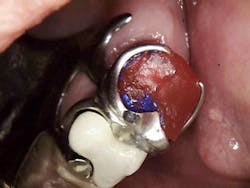

While your assistant is mixing the resin, coat the prepared tooth and RPD clasps with Vaseline. Make a ball of it and then slightly flatten and seat on the prep. Then seat your RPD and start your clean up at the apical portion right away. You won’t have much time but be sure not to pull any material away from the RPD or tooth once you see an initial set.

It’s just as easy to trim it like a provisional once it has set (about three minutes). Your lab can then index the coping for the clasping and occlusal rest when they are finishing the wax-up or ceramics of the crown. You may have some minimal adjusting to do on the clasps when you seat the crown but you’ve insured the best adaptation that the lab can do.